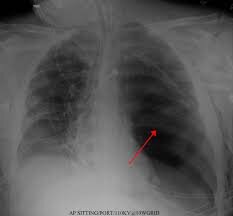

The most common symptoms of lung cancer are chronic and/or worsening cough, shortness of breath with exertion…

Lung cancer is the most common fatal malignancy among both men and women in the United States. Its peak incidence is…

Imaging in lung cancer is far from perfect. A chest x-ray cannot distinguish lung cancer from a…